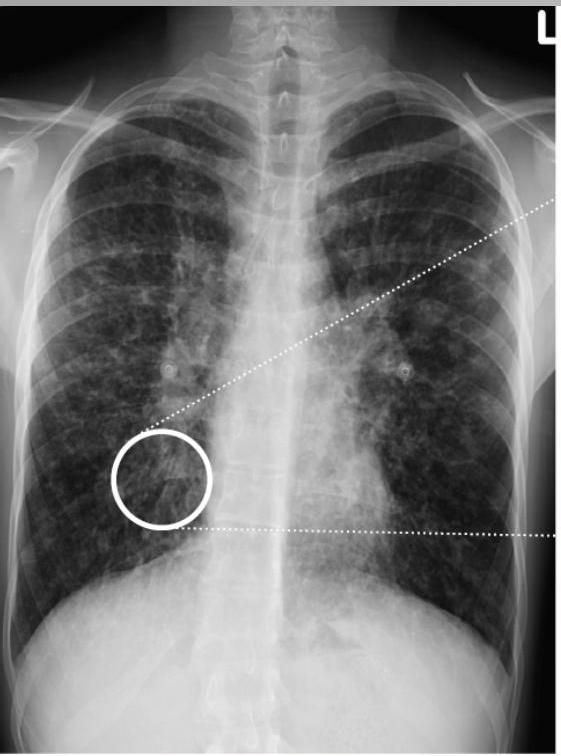

Radiographic Findings (Chest X-ray)

Conglomerating cysts of varying size and wall thickness. “Honeycomb” sign.

- ☐ Chest X-ray: increase in size and loss of bronchovascular markings, crowding of bronchi, and loss of lung volume. Severe case: Honeycombing.